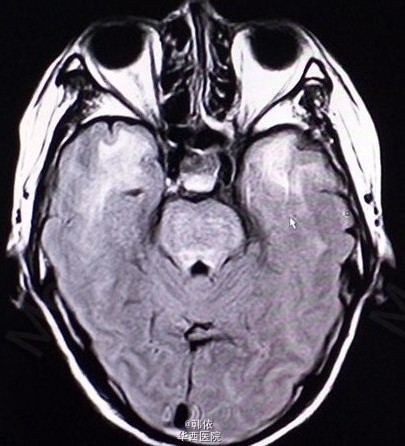

原创:青年男性,因“反复突发意识障碍1+月”入院,1+月前,患者感冒后突发意识障碍,呼之不应,随之出现四肢抽搐,双上肢屈曲、抽搐,双下肢强直,双眼向上凝视,牙关紧闭,小便失禁,无口吐白沫等,持续10+秒后意识恢复,不能回忆,急诊入当地医院治疗,行脑脊液、头部增强MRI等检查,考虑“痫性发作,病毒性脑膜炎”给予降颅内压、抗病毒等治疗,患者住院过程中出现一次右下肢抽动及多次小便失禁,治疗过程中感头部昏沉感,呈持续性,并出现饮水呛咳,治疗效果欠佳。既往患有高血压2+年,未治疗。长期农药接触史2+年。查体:神清,对答切题,高级神经活动正常,双瞳孔等大等圆3mm,对光反射灵敏。四肢肌力肌张力正常,左侧病理征(+),右侧病理征(-),余无特殊。辅助检查:头部MRI示:双侧基底节、双侧丘脑、脑干、双侧小脑及双侧侧脑室旁、双侧半卵圆中心对称性信号异常,考虑中毒性、代谢性疾患可能(见下图)。